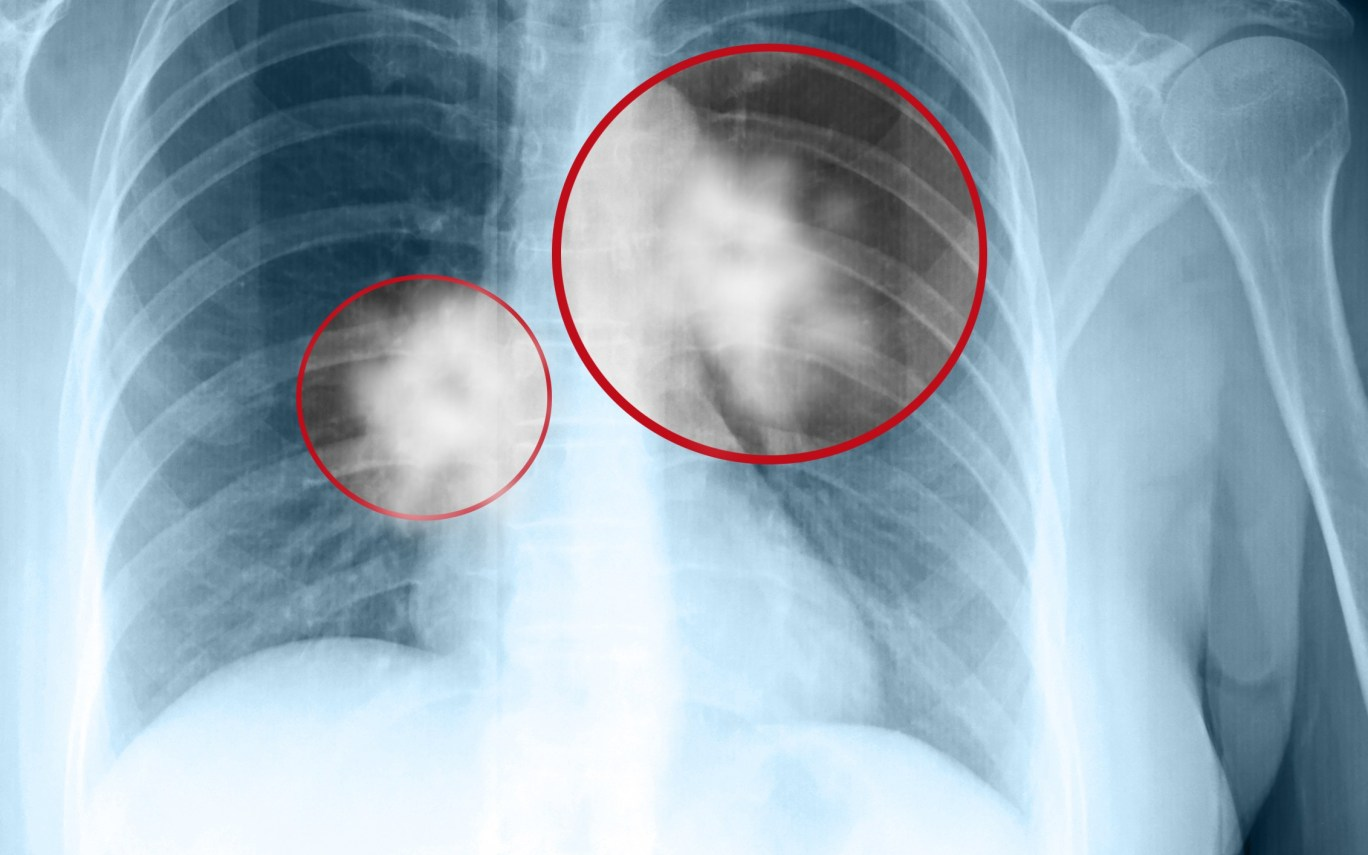

Theo thông tin từ bệnh viện, người vợ, một phụ nữ khoảng 60 tuổi, phát hiện khối u phổi kích thước 3cm khi đi chụp X-quang trong một lần khám sức khỏe tổng quát. Bà cho biết đã vô cùng bàng hoàng. Chồng bà đã qua đời vài năm trước vì ung thư phổi giai đoạn cuối, khi được phát hiện thì dịch phổi đã đầy, chỉ còn sống được một thời gian rất ngắn.